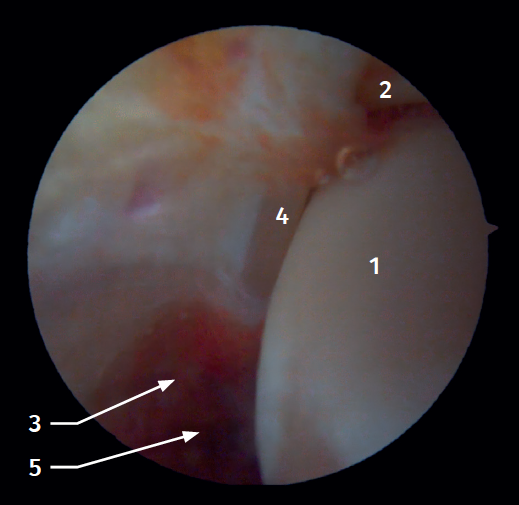

El 20% del LTPA es intraarticular(7). Cuando realizamos un acceso anteromedial del tobillo dirigiendo el artroscopio hacia lateral podemos ver las fibras distales del LTPA con su disposición oblicua y su continuación con el ligamento peroneo-astragalino anterior (Figura 2). Si avanzamos dentro de la articulación tibioastragalina, veremos la articulación tibioperonea distal con el receso sindesmal ocupado de tejido sinovial (Figura 3).

Desde el abordaje posterolateral identificaremos el maléolo peroneo y, desde aquí, visualizaremos las fibras intraarticulares del LTPP, que se dirigen de forma oblicua insertándose en la porción distal de la tibia. También veremos el engrosamiento distal del LTPP (ligamento transverso) en continuidad con el labio posterior de la tibia distal (Figura 4).

Figura 3. Visión artroscópica anterolateral de un tobillo derecho al introducirnos en la tibioastragalina. 1: cúpula astragalina; 2: cara articular de la tibia; 3: peroné; 4: articulación tibioperonea distal; 5: fibras distales del ligamento tibioperoneo anterior.

Figura 4. Visión artroscópica posterior de un tobillo derecho al que le hemos resecado un proceso de Stieda sintomático. 1: ligamento tibioperoneo posterior; 2: ligamento transverso; 3: cúpula astragalina; 4: tibia distal; 5: articulación subastragalina posterior; 6: flexor largo del hallux.